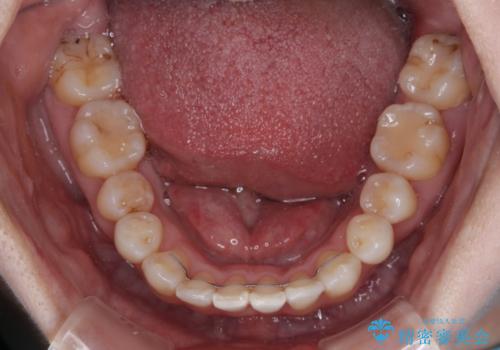

飛び出した上顎前歯と上下のデコボコ 片顎の抜歯によるワイヤー矯正

- 上下前歯のデコボコと、上顎の八重歯を気にして来院された患者様です。

下顎に対して上顎が前方にあり、第一大臼歯による咬合状態は上顎前突であったため、上顎のみ左右の第一小臼歯を抜歯し、ワイヤー装置にて矯正治療を行うこととしました。